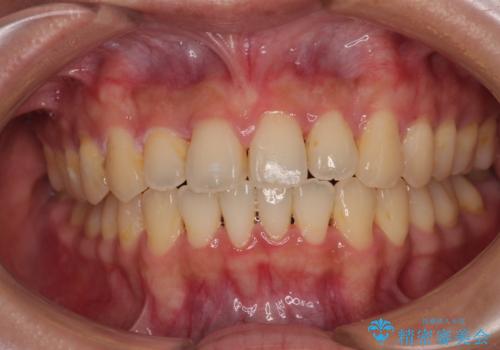

深い咬み合わせと飛び出した前歯 ワイヤー装置での抜歯矯正治療